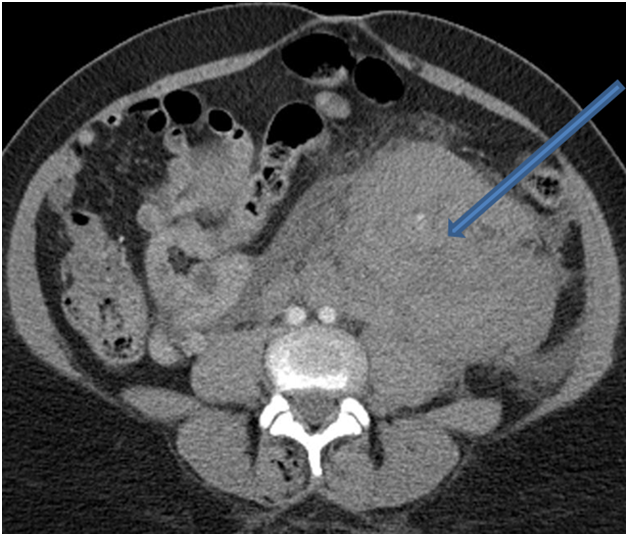

Laboratory tests including complete blood count and coagulation profile were sent. There was a suspicion of retroperitoneal fluid collection on Focused Assessment with Sonography in Trauma (FAST) ultrasound examination of the abdomen. The endometrial thickness was noted to be 0.7 cm. The hemoglobin and hematocrit obtained were 8.6 gm/dl and 26%, which were significantly decreased from 11.9 gm/dl and 36.3% at the time of admission. The coagulation profile was normal with an INR of 1.0. Transfusion of two units of packed red blood cells was started, and a contrast-enhanced computed tomography (CT) scan of the abdomen and pelvis was obtained. The CT showed a large amount of complex fluid in the pelvis extending caudally along the left retroperitoneum to the level of the upper left renal pole with a mass effect on the uterus and left kidney (Figure 1 & 2). The collection contained a prominent, tortuous left ovarian artery coursing through the hematoma with a contrast-filled outpouching measuring 1.6 cm in the mid-portion of the artery which was suspicious for pseudo-aneurysm.

Figure 2 Axial CT image of abdomen and pelvis demonstrates a large left pelvic and retroperitoneal hematoma.